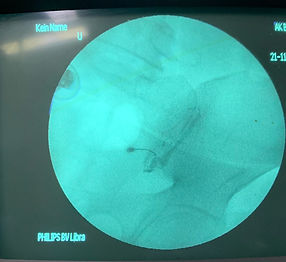

الدكتور غزوان حسن جراح عظام متخصص في جراحة العمود الفقري، ويُركز على الجراحة طفيفة التوغل والجراحة التنظيرية. يُقيم في بغداد، ويجمع بين التدريب الدولي والتقنيات الجراحية المتقدمة والمشاركة الأكاديم ية لتقديم رعاية حديثة قائمة على الأدلة في مجال جراحة العمود الفقري، مع التركيز على سلامة المريض، وسرعة التعافي، والنتائج طويلة الأمد.

مع التركيز الشديد على التقنيات طفيفة التوغل والتنظير الداخلي، نهدف إلى تقليل تلف الأنسجة، وتسريع الشفاء، وتحسين النتائج على المدى الطويل. تُصمم كل خطة علاجية بعناية فائقة لتناسب كل مريض على حدة، حيث ندمج الخبرة السريرية مع التكنولوجيا الحديثة لضمان أعلى معايير الرعاية.